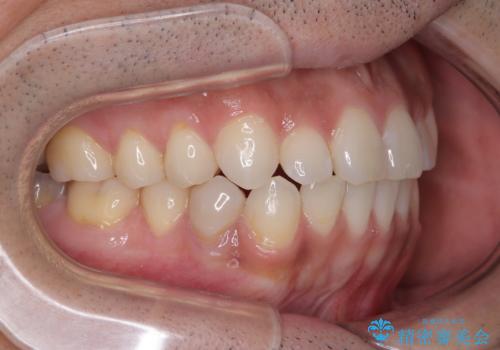

目立たない装置でデコボコを改善 ハーフリンガルによる矯正治療

- 30代男性

- 矯正装置

- ハーフリンガル

- 治療期間

- 1年4ヶ月

- 上下顎歯列のデコボコを改善したいとのことで来院された患者様です。

自己管理の大変なインビザラインや、目立つ表側のワイヤー矯正は避けたいとのことで、

上顎だけ裏側装置のハーフリンガルにて矯正しました。

一年と数か月で矯正を終えることができました。

下顎前歯部には後戻り防止のワイヤーを装着しています。